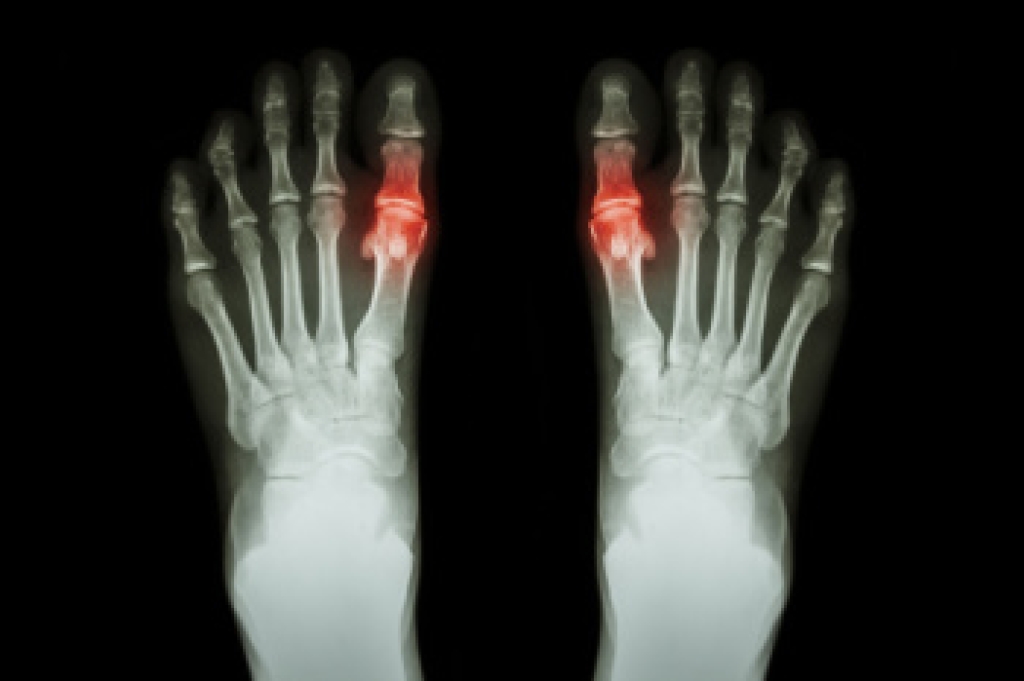

Neuropathy is a condition that leads to damage to the nerves in the body. Peripheral neuropathy, or neuropathy that affects your peripheral nervous system, usually occurs in the feet. Neuropathy can be triggered by a number of different causes. Such causes include diabetes, infections, cancers, disorders, and toxic substances.

Those with diabetes are at serious risk due to being unable to feel an ulcer on their feet. Diabetics usually also suffer from poor blood circulation. This can lead to the wound not healing, infections occurring, and the limb may have to be amputated.